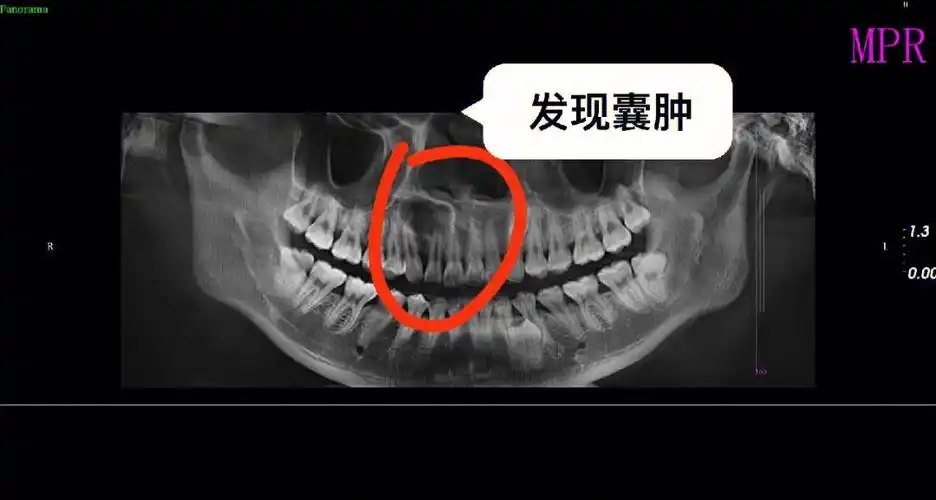

牙齿根尖囊肿应该引起注意